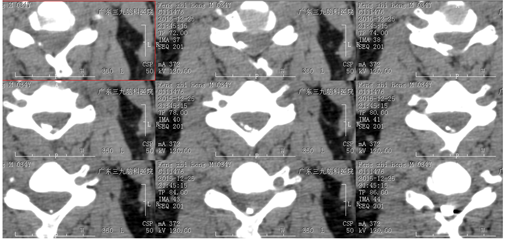

栓塞后CT显示颈4-6水平(偏右后部)栓塞材料高密度影。